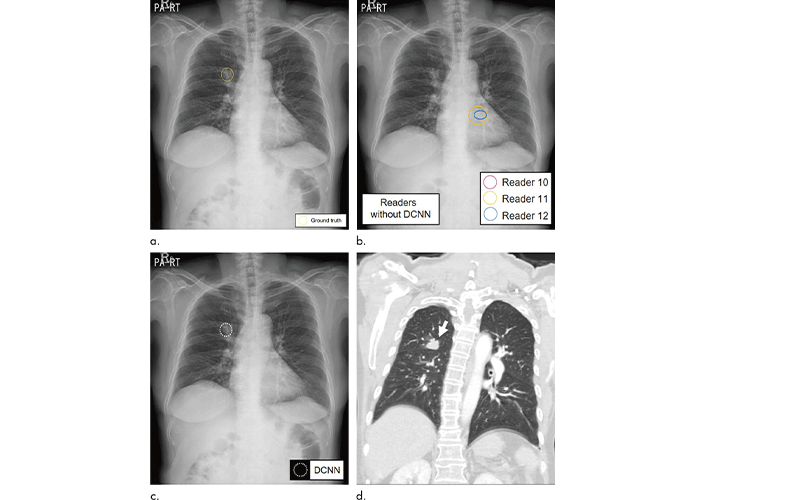

A second group of radiologists, including three from each institution, interpreted the selected chest X-rays with and without cancerous nodules. The readers then re-read the same X-rays with the assistance of DCNN software, which was trained to detect lung nodules.

The average sensitivity, or the ability to detect an existing cancer, improved significantly from 65.1% for radiologists reading alone to 70.3% when aided by the DCNN software. The number of false positives—incorrectly reporting that cancer is present—per X-ray declined from 0.2 for radiologists alone to 0.18 with the help of the software.